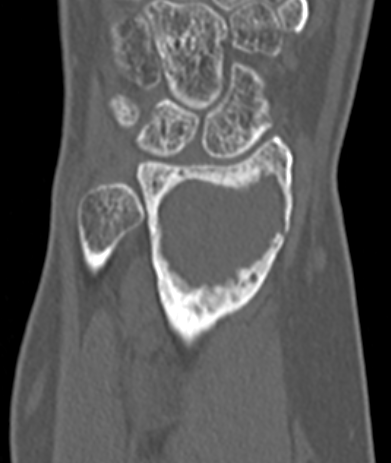

Distal Radius

Abuhejleh et al Eur J Orthop Traumatol Surg 2020

- 57 patients with GCT's of distal radius

- 29% (10/34) recurrence with intra-lesional treatement but no complications

- 4% (1/23) recurrence with wide resection / arthrodesis but 30% complication rate

- increased risk recurrence for Grade 3

- wide resection / arthrodesis should be reserved for grade 3

Koucheki et al Eur J Orthop Traumatol Surg 2023

- systematic review of 13 studies and 373 patients

- increased local recurrence with intralesional versus en-bloc resection

- especially Grade 3

- increased complications and poorer function with en-bloc resection

Distal radius GCT treated with en bloc resection and allograft reconstruction, followed by late wrist subluxation